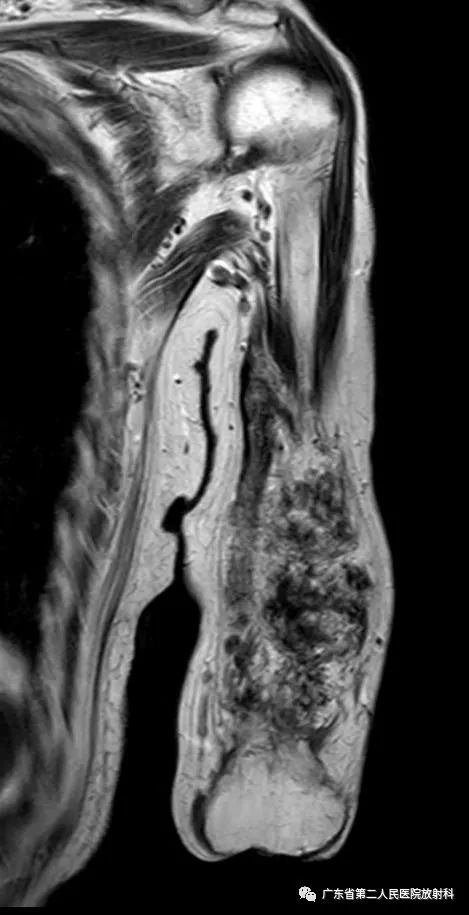

T2WI

左上肢前壁截肢术后观,左上臂中下段见团块状异常信号,病灶信号明显不均,整体以长T1长T2信号影为主,增强扫描呈明显不均匀强化,末端球形膨大,内见散在少许团絮状短T2长T1且无强化信号。冠状位示病灶整体呈梭形改变,边界欠清,部分包绕肱骨下段,以长T1长T2信号为主,散在少许短T2信号,增强扫描明显不均匀强化,内见散在少许团絮状短T2长T1且无强化信号。肱骨下端边缘欠光整,骨髓未见明确异常信号。